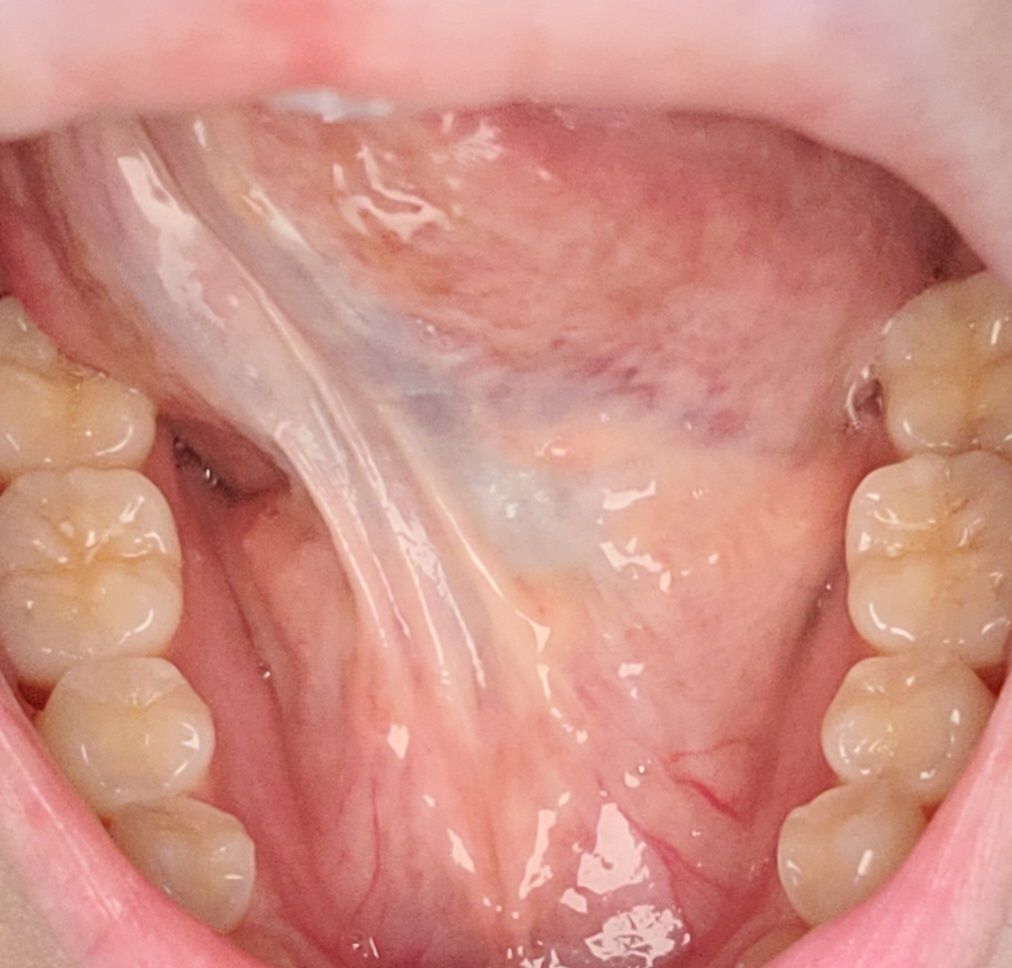

언제부터 있엇는진 모르겠는데 며칠전 확인해보니 혀 밑부분이 전체적으로 하얗게얼룩이 있고 3번째 사진처럼 혀밑 윗부분에도 얼룩이 있습니다 통증은전혀 없는데 저거 발견한 이후로 갑자기 혀가붓고 얼얼한느낌(아프진안음)도나요ㅜㅜ담배술은전혀안해요ㅜㅜ도와주세요 설암일확률 높나요

• 1번 째 사진

• 2번 째 사진